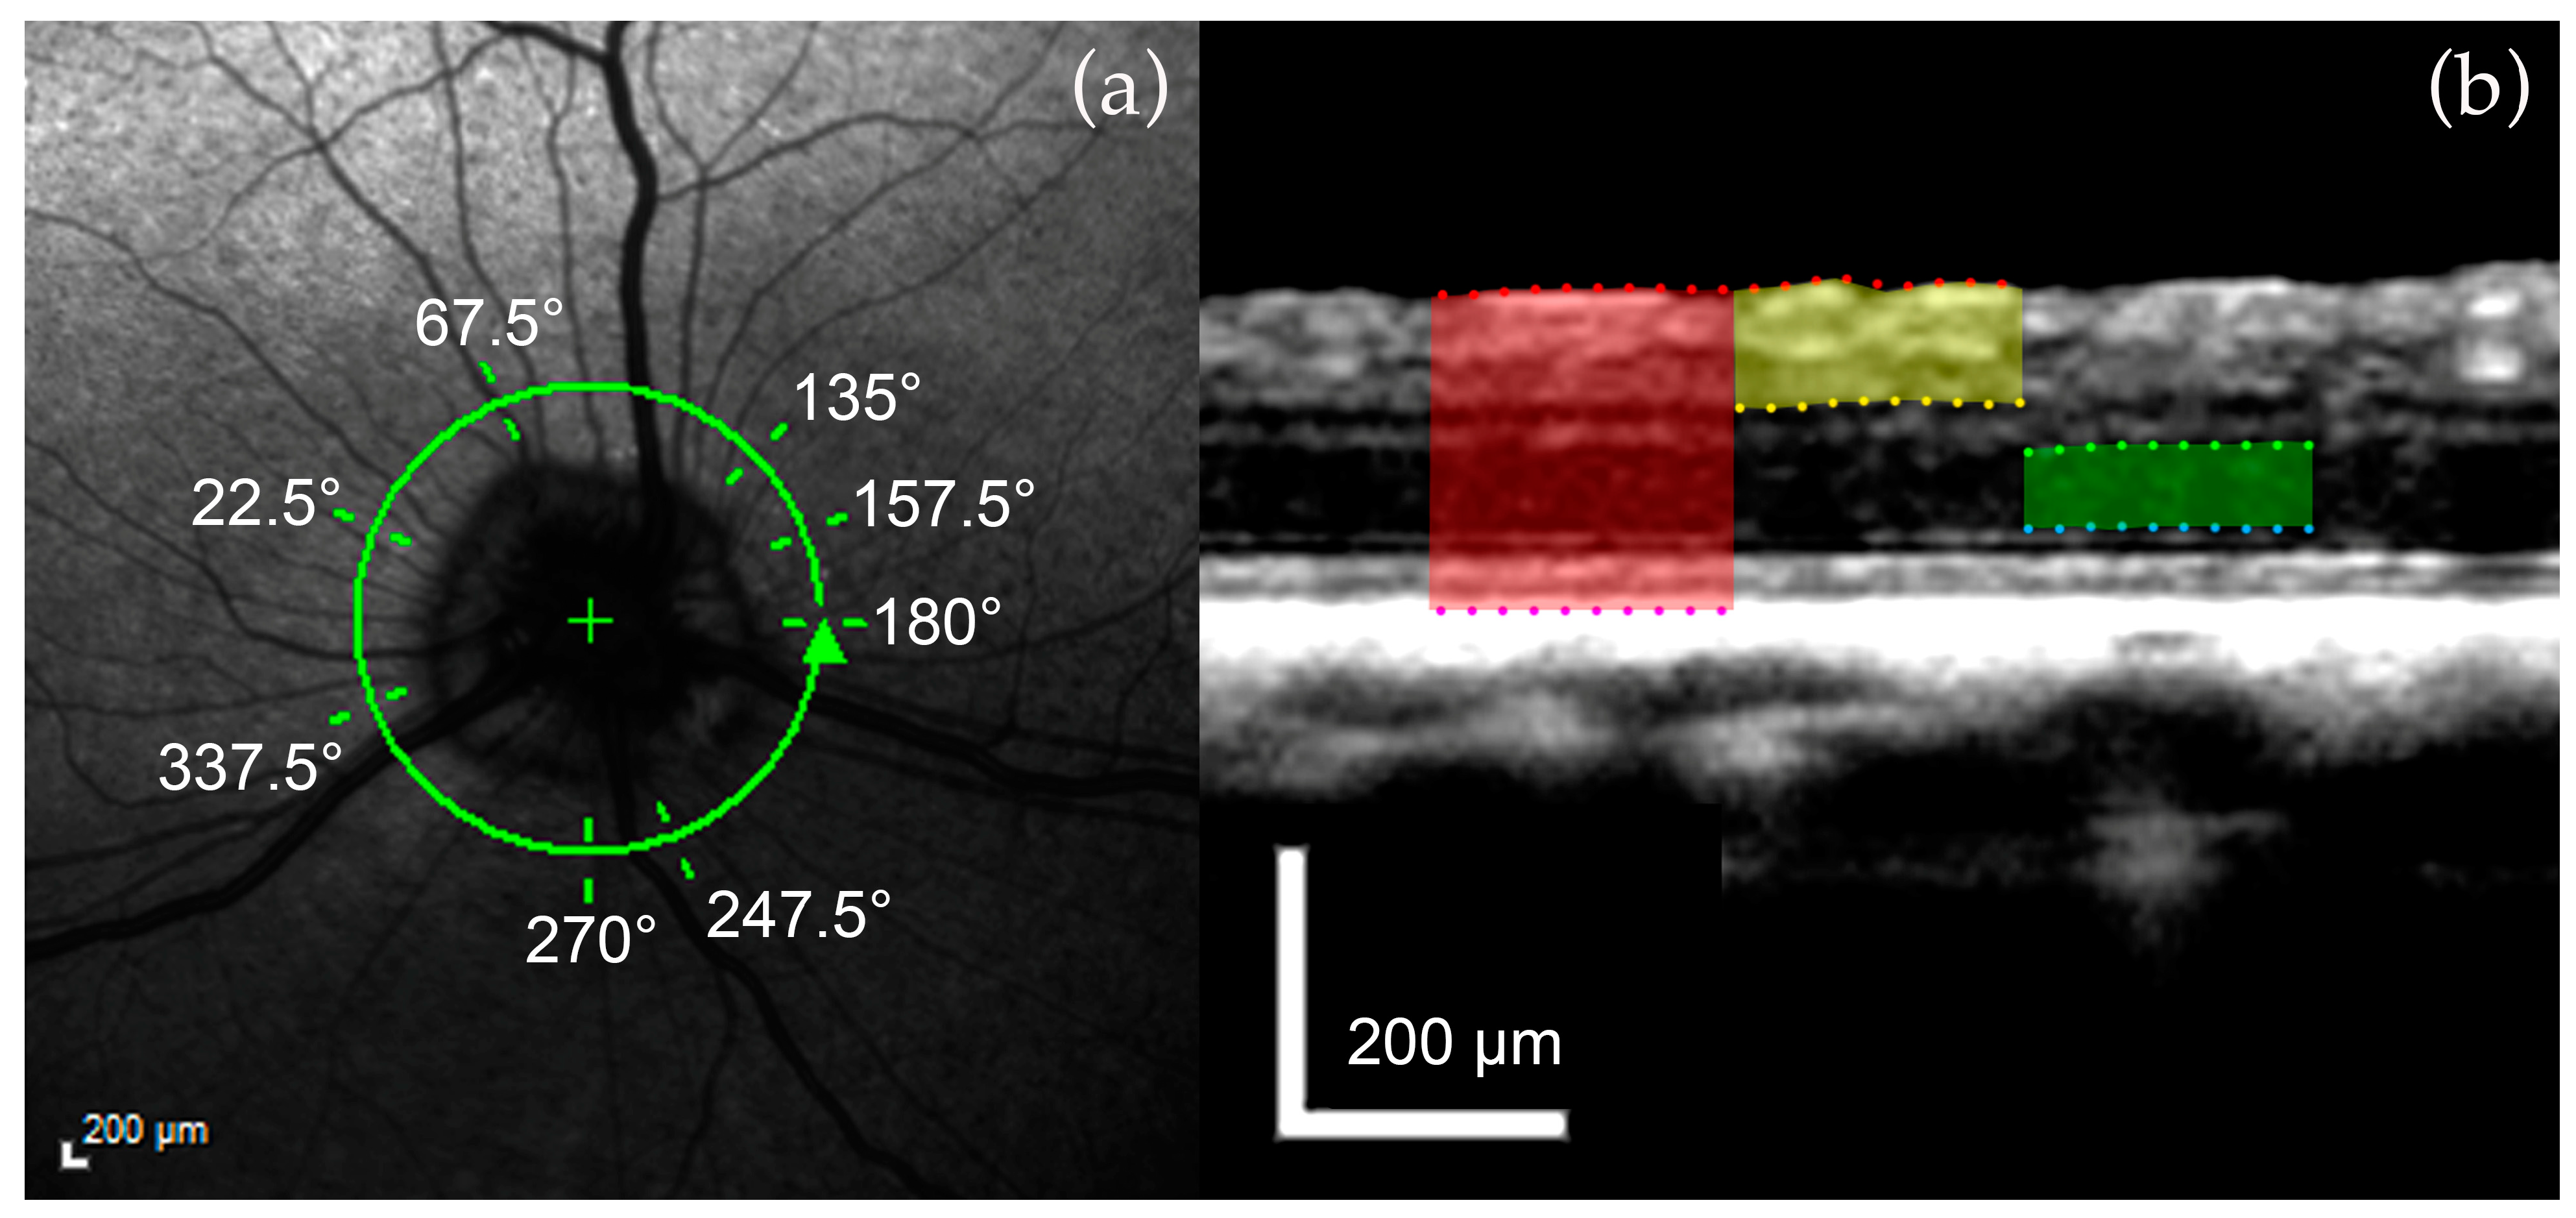

2.3.2. Retinal Layer Measurements

3.2. Retinal Layers